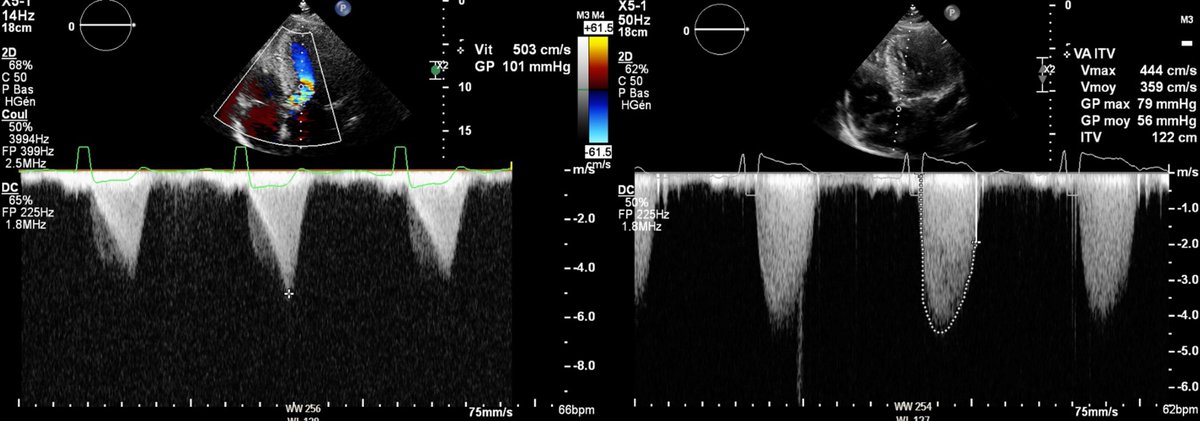

Serial dynamic and fixed LVOT obstruction is a difficult clinical challenge. How severe is aortic stenosis? What is the next step in management? https://t.co/c8FtrqYdJU